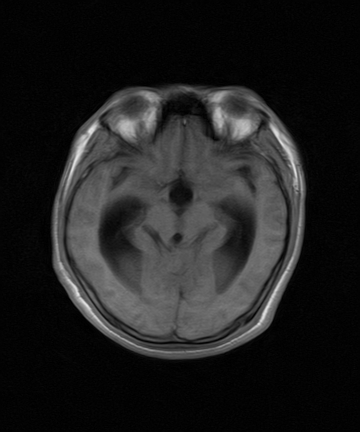

标题: MRI2064:少见病例。男性52,视力下降多年。 [打印本页]

标题: MRI2064:少见病例。男性52,视力下降多年。

四脑室区见混杂信号占位影,脑室系统扩张明显,临近结构显著受压称位,患者52岁,多考虑室管膜瘤可能性大

定位;脑室内富血供占位

1,脑室内血管母细胞瘤。

2,pnte。

3,脑膜瘤。

4,室管膜瘤。

应该是来源于小脑蚓部的占位,如血管母细瘤或星形细胞瘤